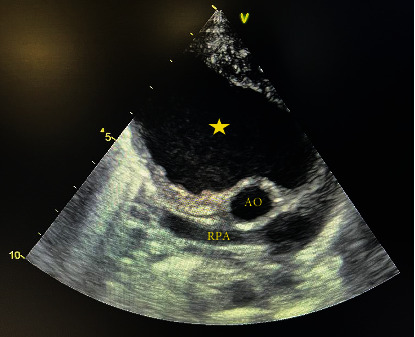

主动脉假性动脉瘤是一种罕见的疾病,其特征是局部的跨壁破坏和主动脉扩张,在儿科人群中非常罕见。它主要是由先前的心血管手术引起的,如主动脉缩窄修复、主动脉瓣置换术和主动脉下膜切除术。我们提出一个独特的病例主动脉假性动脉瘤手术后修复膜周围室间隔缺损在一个19个月大的男孩谁提出发烧作为唯一的症状。术后第30天开始发热,实验室检查结果异常,白细胞(WBC) 28.3 × 109/L,中性粒细胞百分比68%,血小板计数880 × 109/L,红细胞沉降率(ESR) 200 mm/h, c反应蛋白3+阳性。超声心动图示升主动脉内一巨大囊性肿块(5 × 4.8 cm),压迫上腔静脉。基于这一发现,我们怀疑诊断为主动脉假性动脉瘤。经心脏计算机断层血管造影确诊,患者在深低温和循环停止下接受紧急手术修复主动脉假性动脉瘤。不幸的是,我们的病人在手术后不久就死了。

Aortic pseudoaneurysm, a rare condition characterized by localized transmural disruption and dilatation of the aorta, is very rare in the pediatric population. It is primarily caused by previous cardiovascular procedures such as aortic coarctation repair, aortic valve replacement, and subaortic membrane resection. We present a unique case of aortic pseudoaneurysm following surgery to repair a perimembranous ventricular septal defect in a 19-month-old boy who presented with fever as the sole symptom. The fever started on the 30th day after the surgery, and the patient exhibited abnormal laboratory results, including a white blood cell (WBC) count of 28.3 × 109/L, neutrophil percentage of 68%, platelet count of 880 × 109/L, erythrocyte sedimentation rate (ESR) of 200 mm/hour, and 3+ positive C-reactive protein. Echocardiogram revealed a large cystic mass (5 × 4.8 cm) in the ascending aorta, compressing the superior vena cava. Based on this finding, a diagnosis of aortic pseudoaneurysm was suspected. The diagnosis was confirmed through cardiac computed tomographic angiography, and the patient underwent emergent surgery for the repair of the aortic pseudoaneurysm under deep hypothermia and circulatory arrest. Unfortunately, our patient died shortly after the surgery.